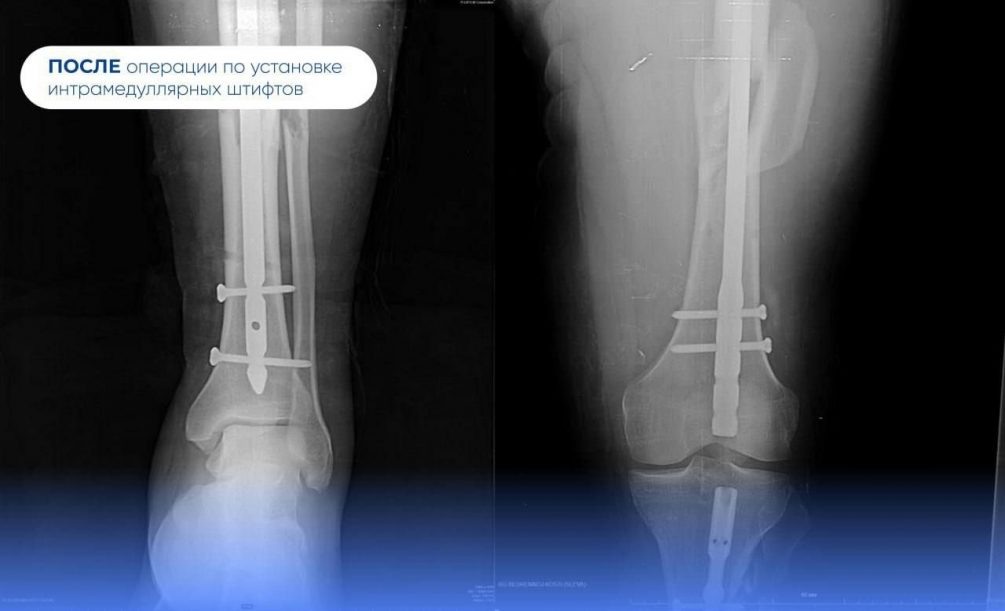

«Через один разрез примерно в пять сантиметров мы установили сразу два внутрикостных штифта — в бедренную и большеберцовую кости. Конструкции будут удерживать отломки в правильном анатомическом положении, создавая условия для скорейшего сращения», — пояснил доктор.

Операцию проводили под постоянным рентген-контролем. Она длилась ровно час. Так врачи смогли добиться цели минимально травматичным способом. Теперь вахтовик проведёт в больнице три недели, в том числе и новогодние праздники. Ему пообещали комплексное лечение, в том числе реабилитационное.